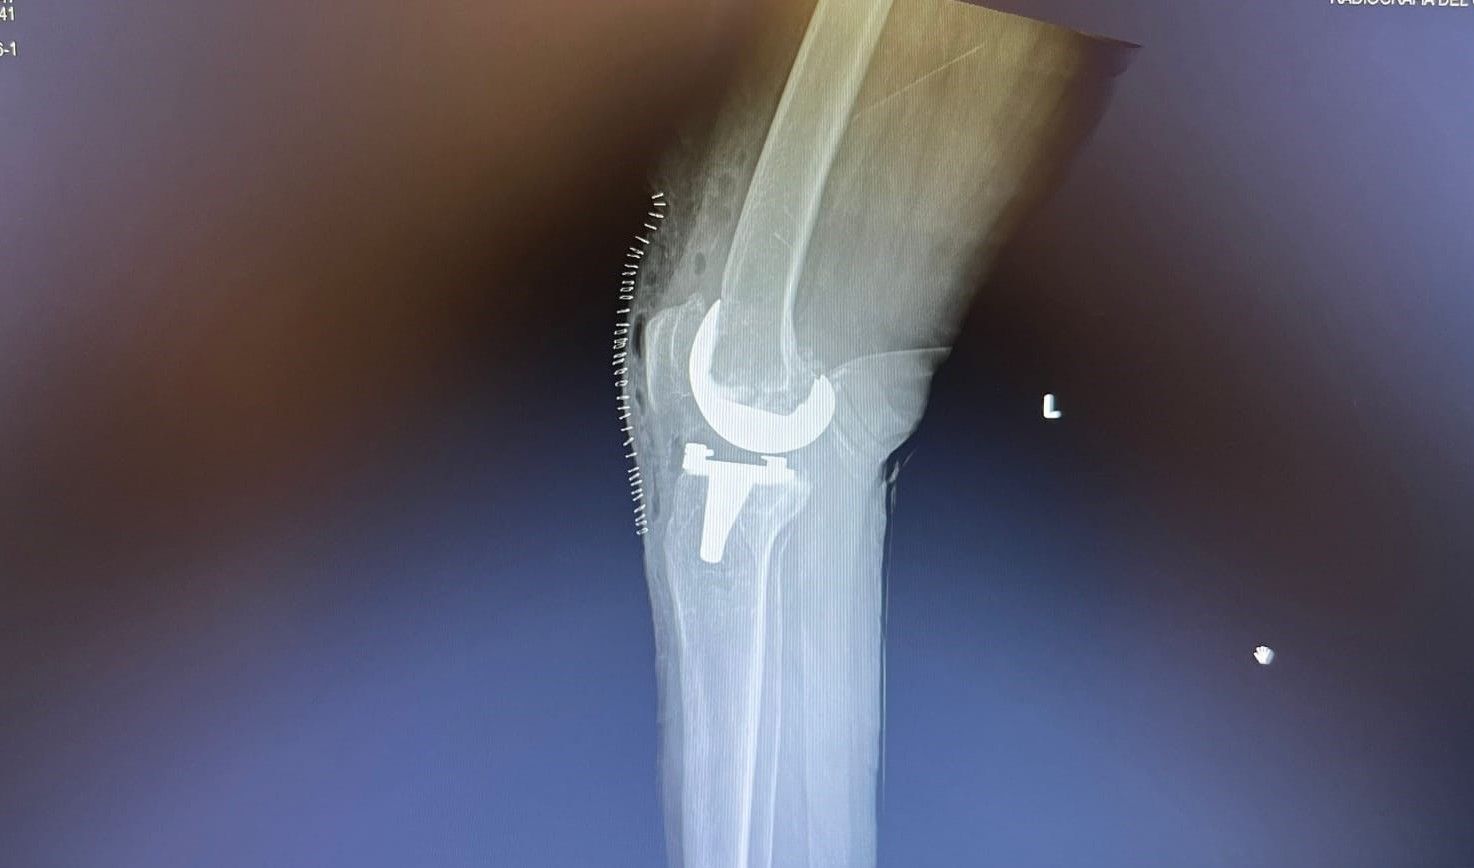

La protesi di ginocchio è costituita da una componente tibiale, una femorale, entrambe in lega di cromo-cobalto, ed un inserto in polietilene che aumenta la congruenza articolare e la stabilità dell’impianto protesico. In genere, le componenti protesiche si fissano all’osso con il cemento, oppure utilizzando degli impianti in tantalio, materiale che si osteointegra completamente entro 3 mesi, senza necessità di cementare.